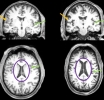

Neuroimágenes antes y después de covid

Incluso los casos ligeros de covid dejan marcan permanentes en el cerebro.